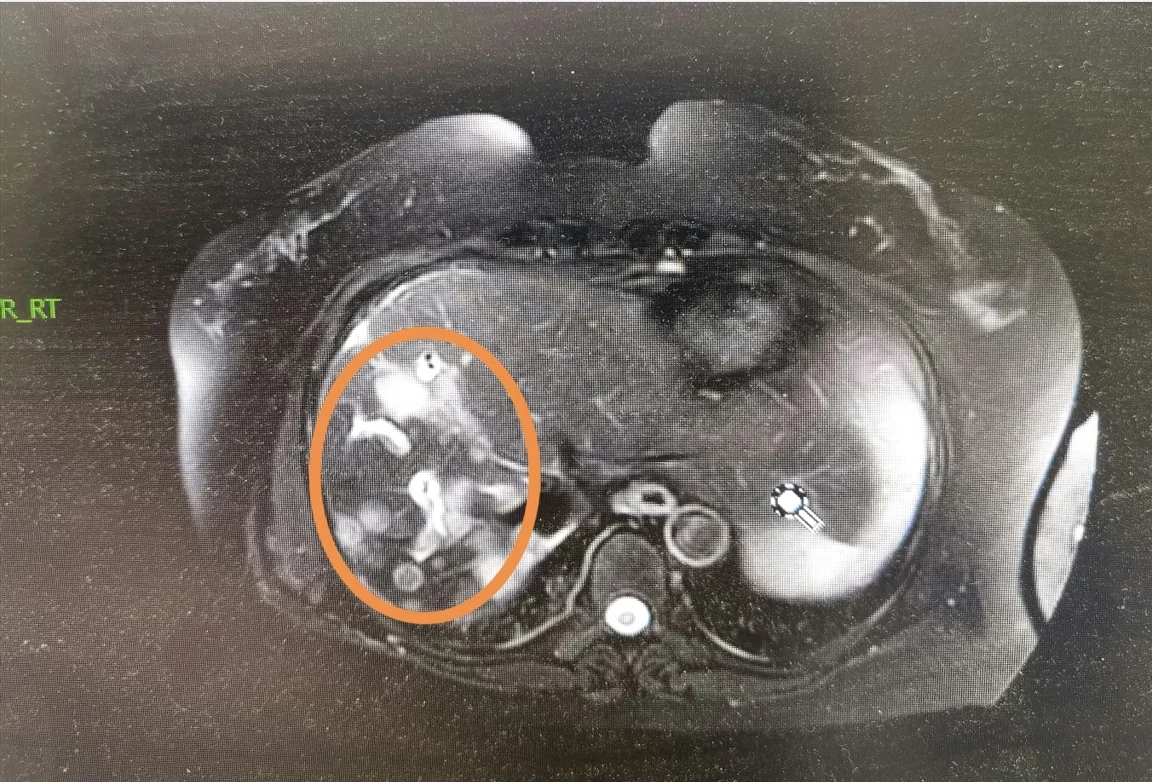

3. 微创技术革新:个体化治疗创造生命奇迹

胆囊癌肝转移患者传统治疗手段有限,5 年生存率不足 5%。但随着介入技术的革新,广州新市医院肿瘤科近日公布的临床案例显示:张俊杰主任团队为其制定了 "微波消融 + 靶向 + 免疫" 的联合方案,通过治疗 3 个月后,患者肝转移灶缩小 75%,CA19-9 从 2500U/ml 降至正常,恢复正常生活,患者精神好,还长胖了几斤,患者和家属均信心大增,后悔没有早点儿找到我。实现了从 "晚期" 到 "可控" 的跨越。